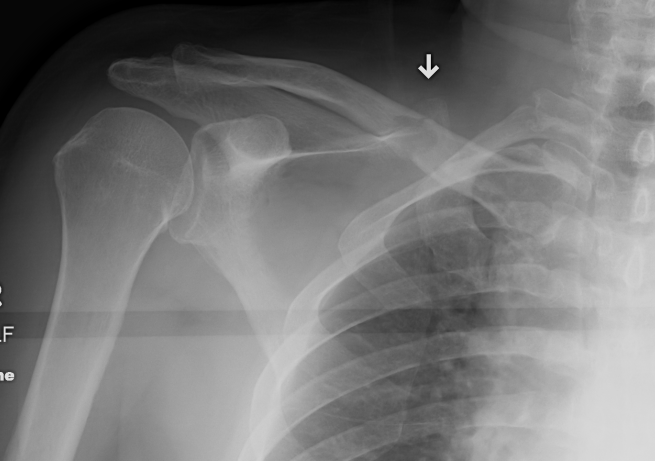

Metastasis with Unknown Origin

Likely Origin / Hexagon / PBBLTK

Thyroid Breast

Background

Aim

The identification of skeletal metastasis & fixation prior to fracture

Incidence

50% of new cancer cases have metastasis

- 1% have pathological fracture

- increasing with more aggressive palliative care